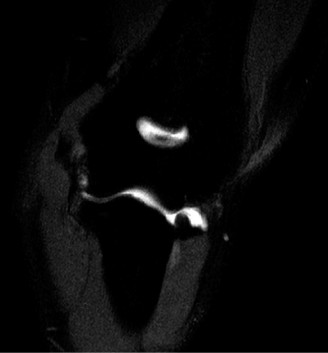

On examination, he has tenderness to palpation over his olecranon and pain with terminal elbow extension. He has no evidence of varus or valgus instability. No pain with resisted wrist flexion. His images are shown (Figs. 2–108 to 2–110).

Figure 2–109

The correct answer is (A). This syndrome occurs most commonly in competitive pitchers, with pain that is worse in the deceleration phase and at terminal extension. The resulting chronic stress results in chondrolysis, osteophyte formation, and attenuation of the MCL. Medial epicondylitis is also common in pitchers, but the pathology is limited to the flexor pronator mass. Pain is over the medial epicondyle and is worse with wrist and forearm flexion. OCD lesions are most common in the capitellum, often present with mechanical symptoms. Olecranon stress fractures result from repetitive abutment into the olecranon fossa. This is a plausible answer, however, the MRI findings are not consistent. MCL rupture is typically acute and is not seen on the MRI shown.

Understand the radiographic findings seen in patients with valgus overload? Identify indications for operative intervention?